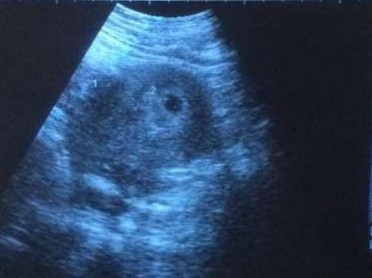

婆婆陪我去妇幼保健院做检查,医生却告诉我,我的血hcg大于1000,说明我怀孕了,但是我的宫腔内却找不到孕囊,而我的右侧附件区有一个小包块。

医生告诉我,我是右侧间质部妊娠,通俗的说,就是宫外孕。因为我之前体检身体条件都很好,没有妇科病,也没有输卵管堵塞,一般情况下不可能会宫外孕呀!